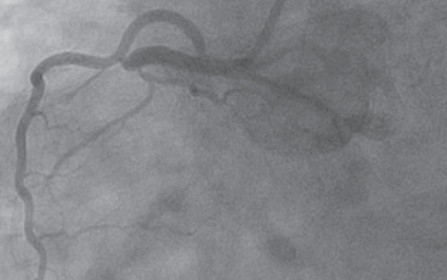

(From top to bottom): A “culprit” lesion in the proximal right coronary artery, post intervention result, and left ventricle placement of the Impella mechanical circulatory assist device to sustain cardiac output.

Patients with clear evidence of a myocardial infarction are routed immediately to the catheterization lab to undergo percutaneous coronary intervention (PCI) to open blocked coronary arteries. Smith adds, “We typically initiate PCI in appropriate patients,” in line with the 2010 AHA Guidelines for CPR and Emergency Cardiovascular Care5 which state “coma and the use of induced hypothermia are not contraindications or reasons to delay PCI…[and] PCI after [return of spontaneous circulation] in subjects with arrest of presumed cardiac etiology may be reasonable, even in the absence of a clearly defined ST-segment elevation myocardial infarction (STEMI).” Cooling and PCI may also be performed concomitantly. Large case series reports2,3 seem to indicate that early and successful PCI is associated with improved odds of survival for most patients with OHCA. Other positive prognostic signs include: time from collapse to basic life support less than five minutes; non-diabetic; age less than 59 years; initial rhythm marked by ventricular tachycardia or ventricular fibrillation; and presence of ST elevation. Additional tools such as extracorporeal membrane oxygenation (ECMO) and ventricular assist devices, can serve as what Smith refers to as “a bridge to decision,” supporting the patient while longer-term treatments are considered or prepared.